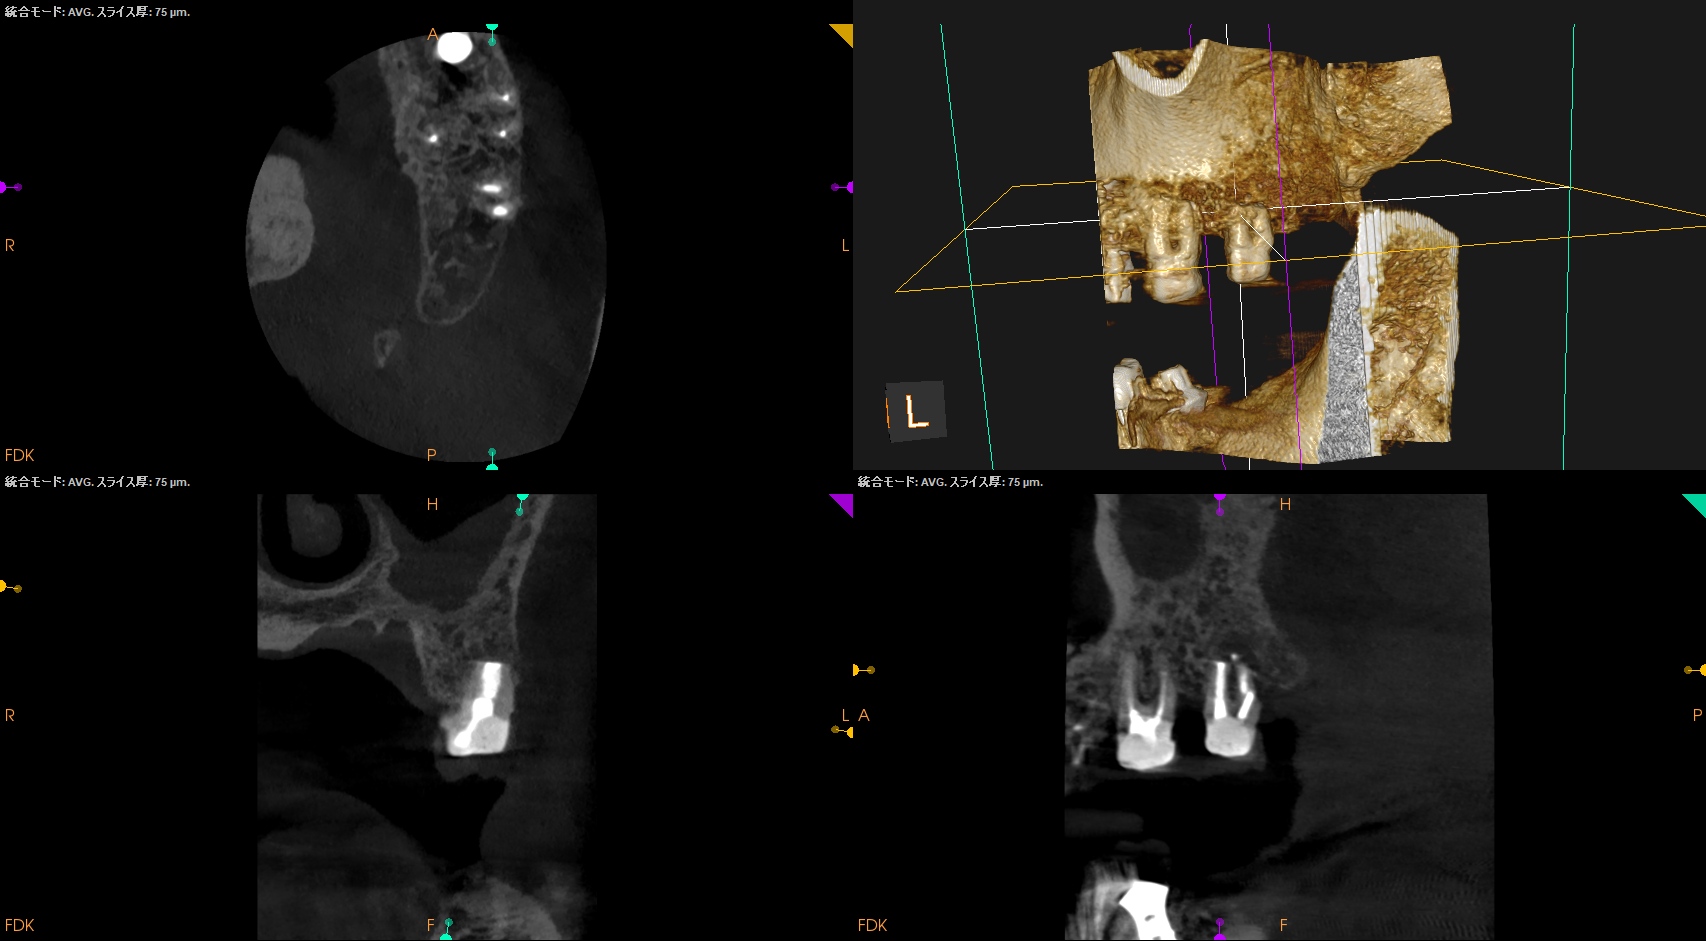

#15 Intentional Replantation 6M recall(2025.10.8)

治療直後と比較した。

歯槽骨の改善が大幅にみられた。

次回はさらに半年の1yr recallである。